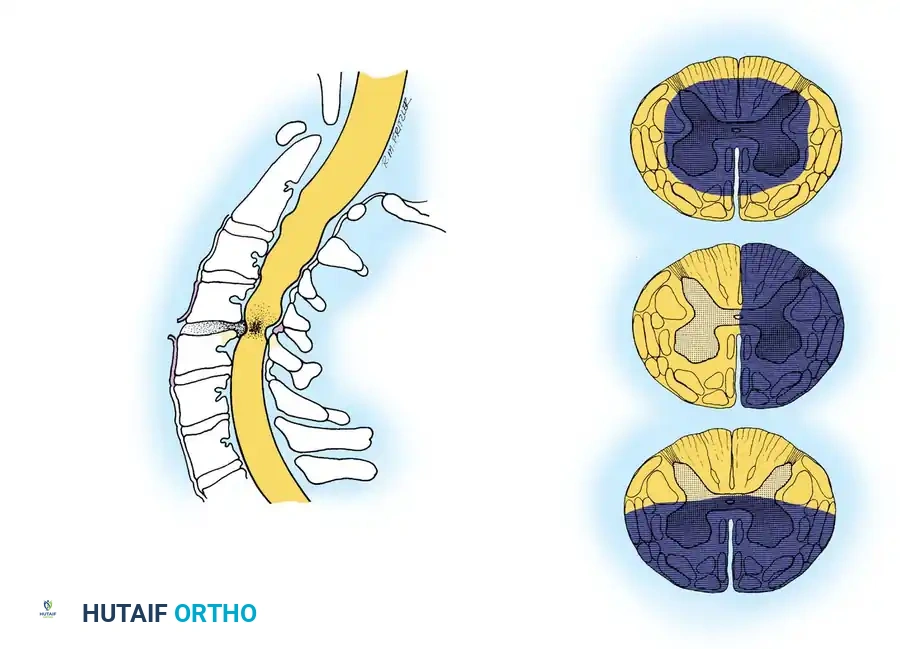

Brown-Séquard Syndrome

This syndrome results from a functional hemisection of the spinal cord, often due to penetrating trauma (e.g., stab wounds) or severe unilateral facet dislocations.

* Clinical Presentation: Patients exhibit ipsilateral loss of motor function (corticospinal tract) and proprioception/vibratory sense (dorsal columns), combined with contralateral loss of pain and temperature sensation (spinothalamic tract) beginning one to two levels below the lesion.

Anterior Cord Syndrome

Anterior cord syndrome is caused by a hyperflexion injury resulting in anterior spinal artery compromise or direct anterior compression from a retropulsed bone fragment or massive disc herniation.

* Clinical Presentation: Complete loss of motor function, pain, and temperature sensation below the level of injury. Proprioception, vibratory sense, and light touch are preserved because the posterior columns (supplied by the posterior spinal arteries) remain intact.

* Prognosis: This syndrome carries the poorest prognosis for functional motor recovery among the incomplete syndromes.